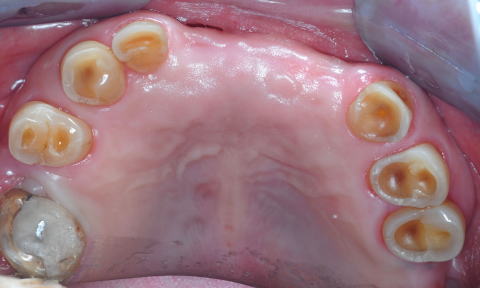

■症例3:酸食症 Acid Erosion

患者:75歳、女性。

ドレッシング、オレンジ、“酢の物”さらに黒酢が好物で、毎日常用。数十年の結果、大切なEnamel質は消失し、咬合高径まで低くなってしまった

■症例2:酸食症 Acid Erosion

患者:73歳、女性。

咬合面Enamel質はすべて溶解している。数十年間毎日“酢の物”を食べ、おまけに残った小皿の“酢”まで飲んでいた。さらに研磨剤入りの歯磨剤を使用していたのが、酸食症に拍車をかけた。“酢”を止め、歯磨剤をリンスに変更し、内科的Diathermyを透射すれば、知覚過敏は即座に消退した